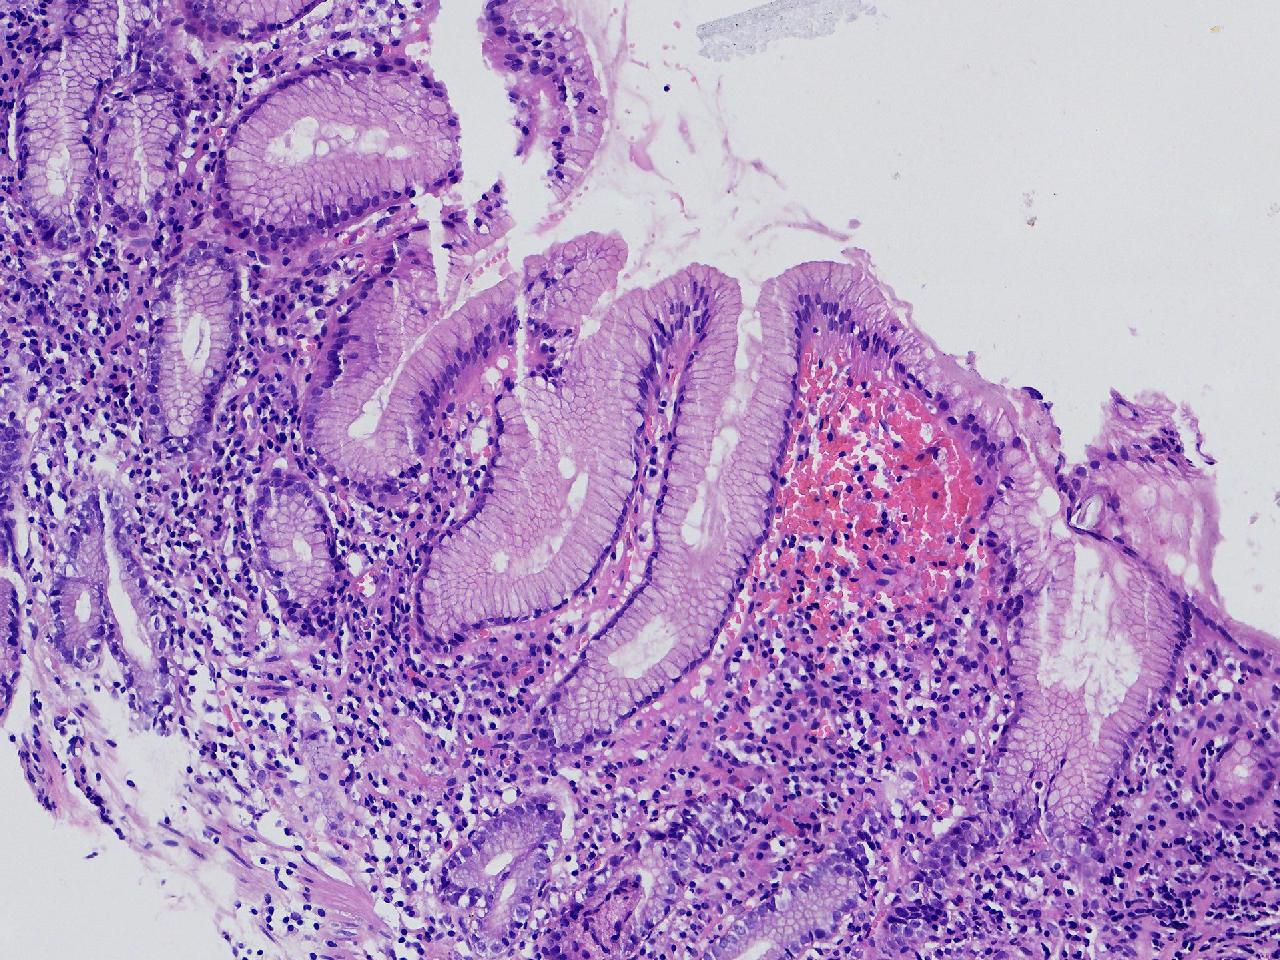

间质内是炎细胞吗?

男,49岁,胃镜活检,胃窦粘膜红白相间,以红为主,后壁见一直径约0.4cm大小片平隆起,表面糜烂,活检1块送检,质软弹性可。

胃窦活检

灰白色不整形软组织1块,直径0.2厘米。

是!还有组织细胞

幽门型粘膜中度慢性炎

是的,主要是淋巴细胞和浆细胞。